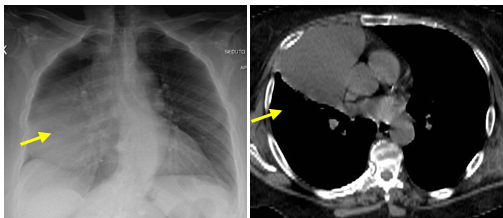

The large pericardial cyst was not clearly dissociable from the pericardium (Figure. 2).

Figure 2. The large pericardial cyst was not clearly dissociable from the pericardium (yellow arrow)